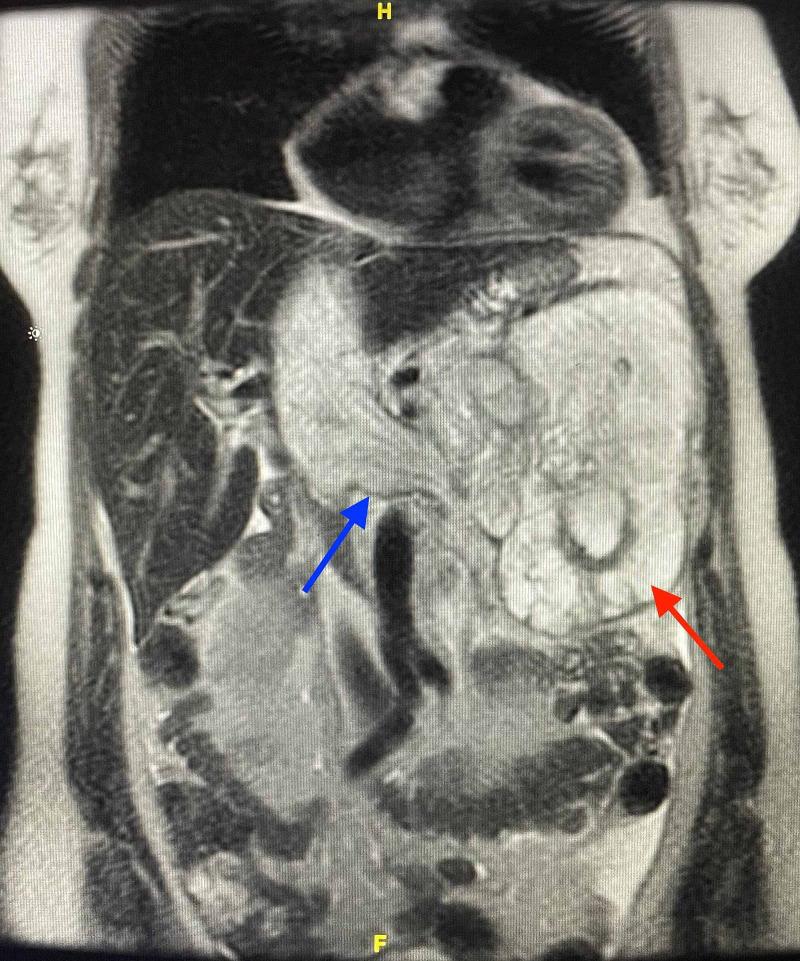

Inoperable Left Renal Vein Leiomyosarcoma Refractory to Chemotherapy Invades Inferior Vena Cava and Right Atrium: A Case Report.

Mesenchymal stem cells differentiate into a plethora of cell types. These differentiated cell types include osteoblasts, chondrocytes, myocytes, and adipocytes. Sarcomas occur secondary to malignant transformation of these mesenchymal, pluripotent stem cells. Involuntary smooth muscle is responsible for the make up of hollow organs and vasculature in our body and is regulated by our autonomic nervous system, hormones, as well as chemical and local mediators. Cancer involving smooth muscle cells is designated as leiomyosarcoma (LMS). LMS can arise from any location in the body where smooth muscle is present and is frequently reported in the abdomen and pelvis, as well as the trunk, extremities, and throughout the retroperitoneum.